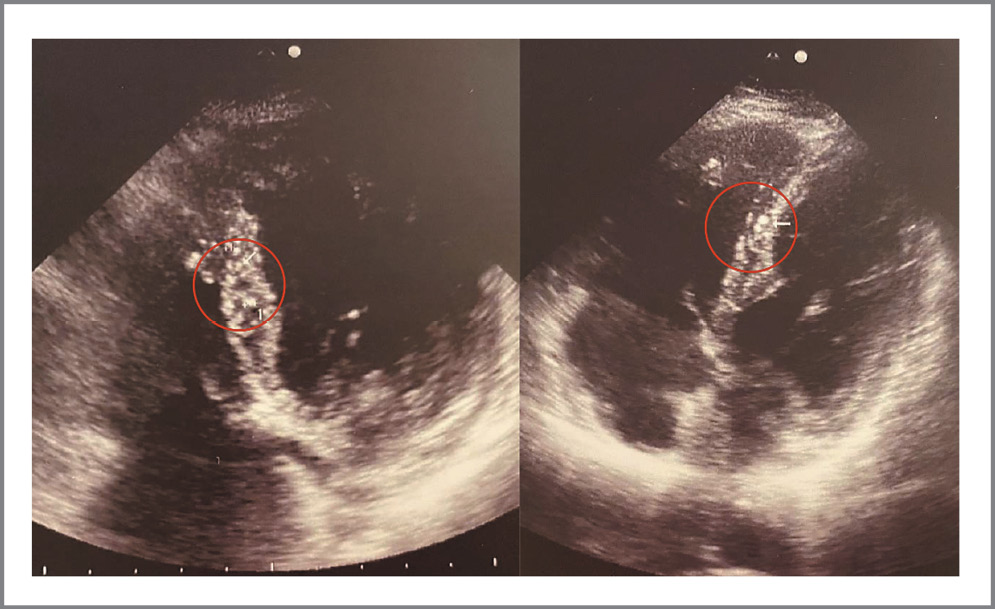

Изменения в миокарде представлены в виде округлых гиперэхогенных, единичных или немногочисленных диффузно расположенных включений от 1,5 до 3,2 мм в диаметре, локализующихся в основном в межжелудочковой перегородке или в толще задней стенки ЛЖ (рис. 4). Эти включения визуально отличались от обычно выявляемых участков мелкоочагового фиброза, например после перенесенного миокардита или при ишемической болезни сердца и кардиосклерозе, когда очаги носят преимущественно линейный характер (рис. 5). Относительно диастолической дисфункции достаточно сложно сделать однозначный вывод, так как к данному состоянию могут приводить различные факторы. Однако наличие включений в миокарде, которые гипотетически могут быть последствиями специфического миокардита или изменениями на фоне перенесенного ТМА-подобного состояния при COVID-19, и гидроперикарда соотносятся с результатами немецкой когорты пациентов [37]. Важно отметить, что обнаружение описанных изменений требует от специалиста ультразвуковой диагностики высокой квалификации и достаточного уровня насмотренности. В течение периода набора данных в поле зрения также попал пациент 21 года, не болевший COVID-19, но у которого по данным ЭхоКГ в миокарде обнаружена группа мелкоочаговых округлых гиперэхогенных включений до 2,5 мм с сохранной диастолической и систолической функцией (рис. 6).

Рис. 4. ЭхоКГ, апикальная 4-камерная позиция, примеры включений в толще межжелудочковой перегородки.

Fig. 4. EchoCG, apical 4-chamber position, examples of inclusions in the thickness of the interventricular septum.